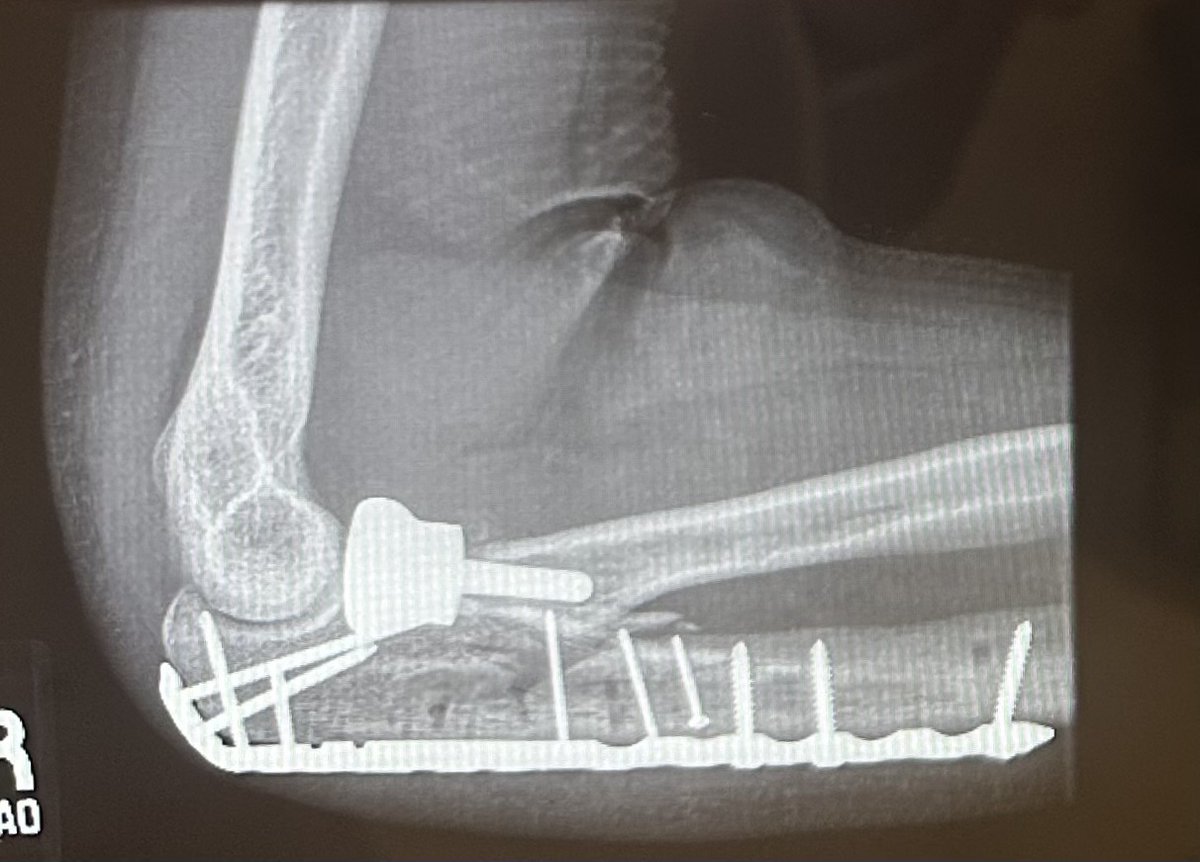

Shout-out to dr Lucas and the SCVMC ortho surgery dept. 🦾🏥Doctors keep telling me it exceptional to recover this well from a catastrophic fracture like this. Closing the chapter on PT soon and moving on to strength training. Limited supination should improve still.